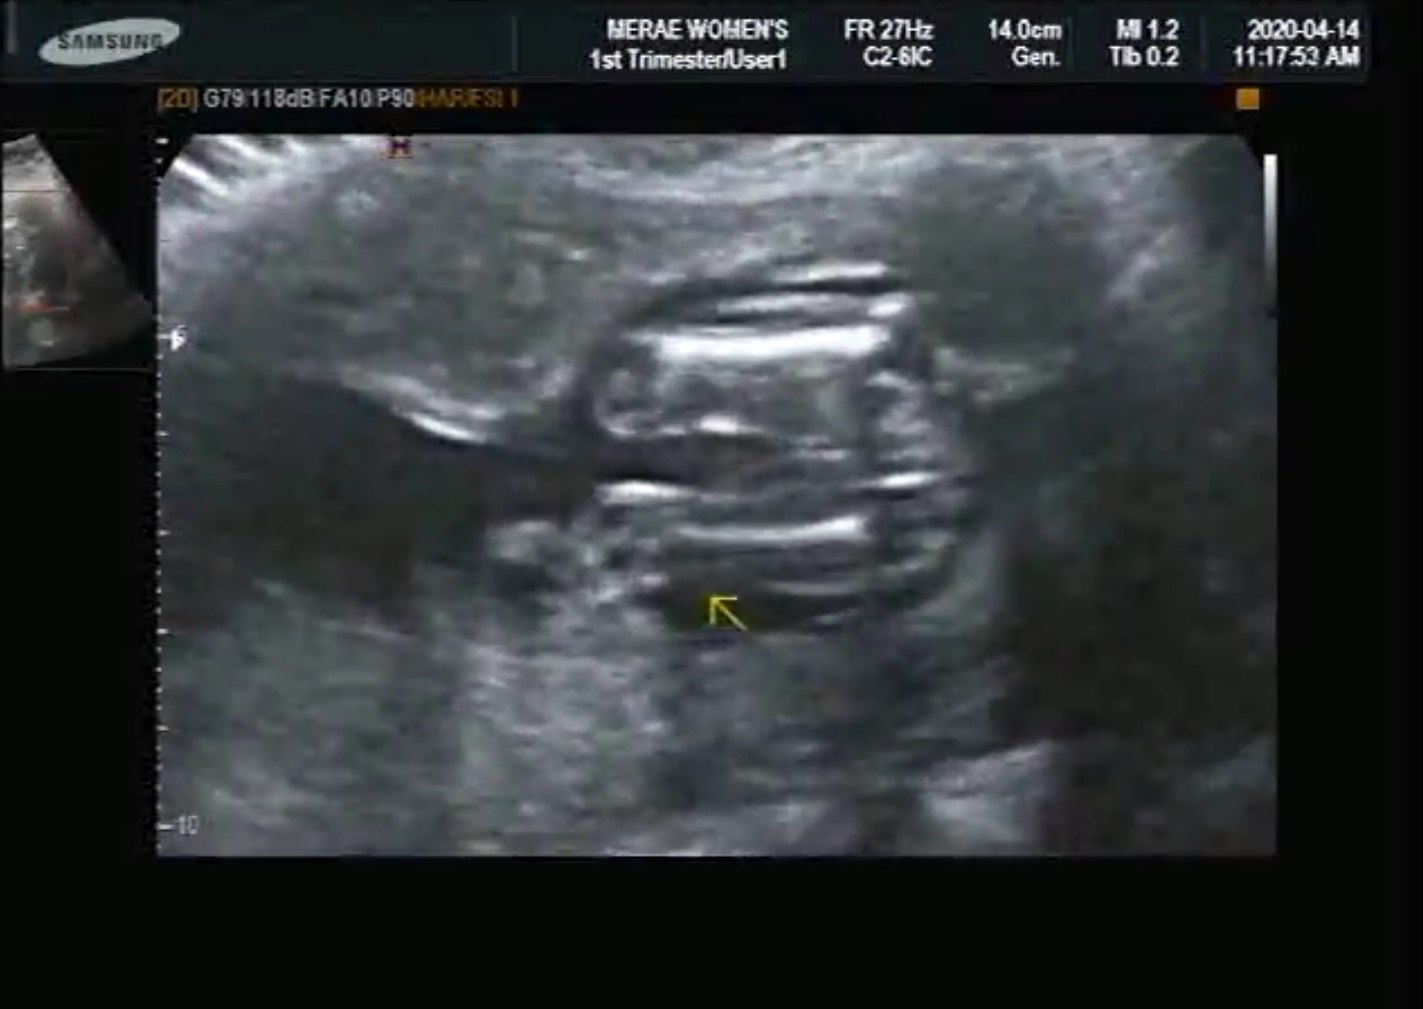

임신 16주차.

천사아기의 눈 코 입 다리 척추 다리 목뼈등 모든것이 제대로 갖추어졌다고 합니다.

끝으로 정말 건강하다고 합니다.

흐뭇한 미소가 자동으로 얼굴에 만들어지네요.

16주 큰자 엄마 배안에서의 움직임

16 weeks of movement in the mother's mother